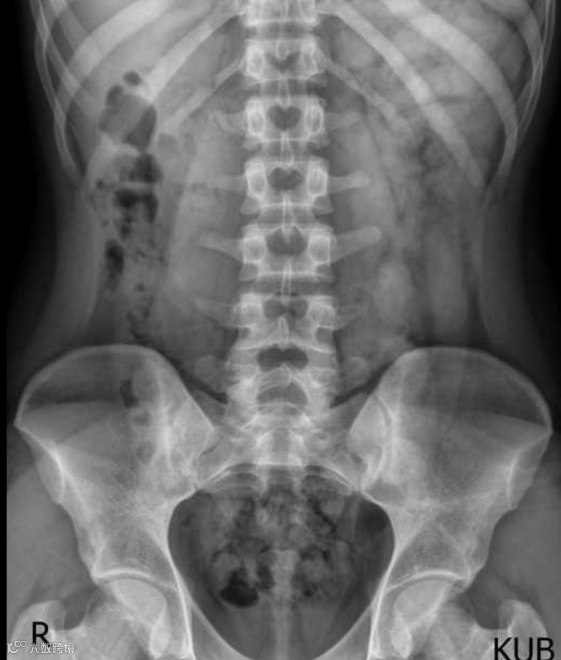

男,20岁,马蹄肾。KUB显示中线两侧各有一软组织肿块,中央可见峡部。注射造影剂后,肾盂肾盏系统的走向清晰可见。双肾下极最靠近中线,这与正常情况相反。双肾均呈旋转状,下极融合,在L3-L4水平形成峡部。